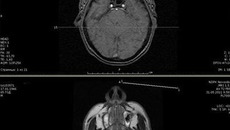

Цифровое ядро клиники Мешалкина — система передачи и хранения данных PACS. К ней подключено пять томографов, шесть рентген-аппаратов, три аппарата УЗИ и три ангиографа, с помощью которых исследуются кровеносные сосуды. Данные с этих аппаратов, например рентгеновские снимки, сразу же попадают в компьютерную базу данных.

По закону истории болезни должны храниться в архиве медицинского учреждения 25 лет. До того, как в клинике Мешалкина была смонтирована система PACS, эта ценнейшая информация хранилась на обычных компьютерах и компакт-дисках. Риск потерять эти данные был достаточно высок, да и поиск в такой разношерстной базе данных был весьма затруднителен. Теперь у медиков есть полная картина всех исследований клиники с почти мгновенным доступом к нужным снимкам.